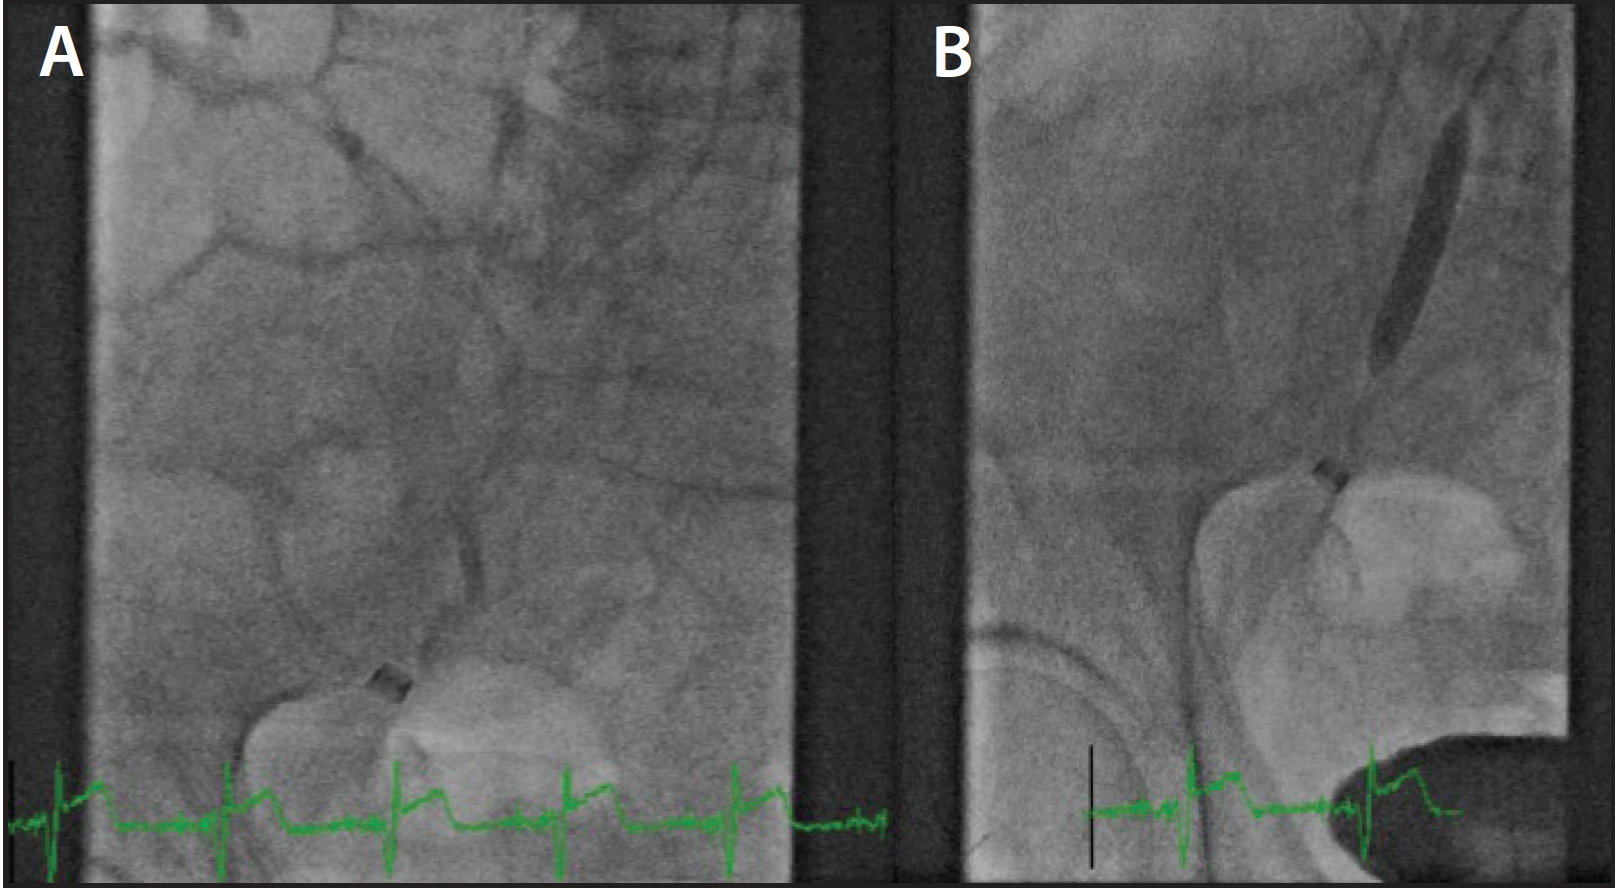

Figure 6. A 7-F, 90-cm sheath was inserted in the right atrium over a 0.035-inch J wire (A). Biopsy forceps were advanced, and ventricular septal biopsy was performed with two-dimensional echocardiography (B).

RHC and endomyocardial biopsy are common procedures for patients with heart failure, heart transplantation, and for the diagnosis of infiltrative myocardial disease. IJ or FV accesses are predominantly used for these procedures. A retrospective study performed comparative analyses between the RHC and biopsy performed via neck vein (594 cases) versus AVA (141 cases).10 Procedural complications were low (n = 7; 0.6%) and were only associated with the neck approach. Patients surveyed preferred the arm approach. The study concluded that RHC and endomyocardial biopsy through the brachial vein could be performed safely, timely, effectively, and at equivalent cost compared with a neck approach. We preferred the AVA for this procedure, which is shown in Figure 6.